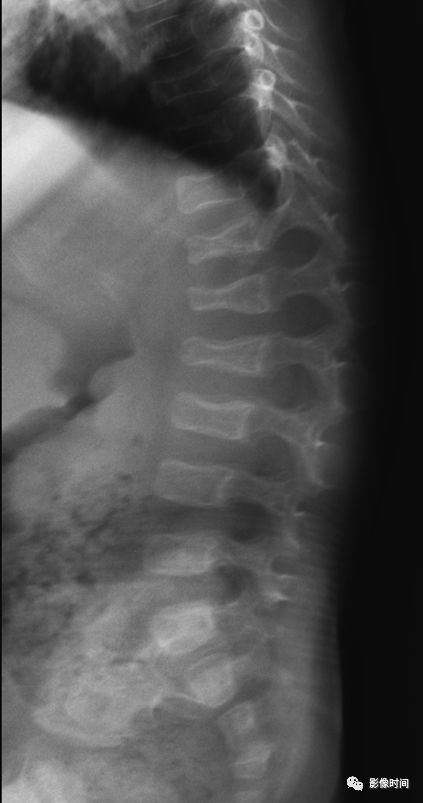

5倒置拿破仑帽征

倒置拿破仑帽征(inverted napoleon hat sign),亦有译为反拿破仑帽征

倒置拿破仑帽征是指在腰椎正位 X 线片中,腰 5 与骶 1 的投影轮廓重叠,形似倒置的拿破仑帽(蓝箭)。其中帽子的边缘是腰 5 的横突形成,而帽子的圆顶是由腰 5 的椎体投影构成。

本征象主要用于描述腰 5 椎体前滑脱(这种滑脱通常为先天性或创伤性,退变性的少见),在腰 5 未滑脱但腰骶部显著前凸时也可以出现此征象。

典型病例

22 岁男性,腰椎侧位片可见腰 5 椎体呈梯形(黑箭头),显著向前、下滑脱(黑箭),正位片形成倒置拿破仑帽征(白箭)。